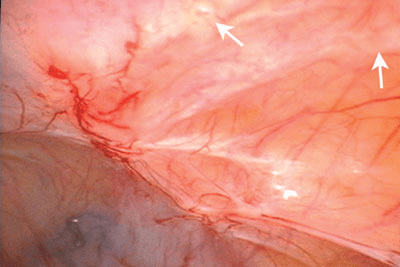

Figure 1. Les lésions symptomatiques d’endométriose du diaphragme (voir flèches) sont habituellement situées sur la partie postérieure de l’hémidiaphragme droit. Cette zone n’est pas facile à explorer à l’aide du laparoscope introduit par le nombril, mais est toujours visible lorsqu’on utilise un laparoscope de 5 mm avancé à travers la gaine musculaire située au-dessous du rebord costal droit, comme on peut le voir ici.